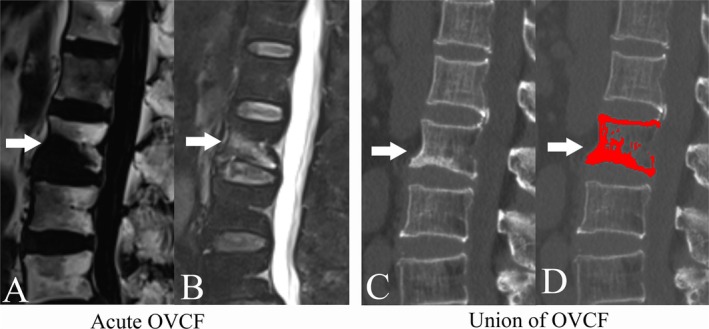

Objective: Increased marrow fat fraction (MFF) of vertebrae was detected in patients with osteoporosis. However, MFF of the fractured vertebrae decreased significantly following the fracture. The aim of this study was to assess the predictive value of fractured vertebrae MFF quantified on T2-weighted Dixon sequences for the prediction of nonunion risk of acute OVCF.

Materials and methods: Medical records of 39 patients with OVCF, including a total of 60 fractured vertebrae, were reviewed retrospectively. Fractured vertebrae in the acute phase were grouped into the nonunion group (20 vertebrae) and the union group (40 vertebrae), based on the OVCF prognosis confirmed by computer tomography (CT). MFF of the fractured vertebrae was quantitatively assessed with the software Matlab on T2-weighted Dixon sequences. Interclass correlation coefficients (ICC) were analyzed to assess the repeatability of MFF measurement. Binary logistic regression analysis was performed to determine the relative contribution of the MFF for predicting the prognosis of OVCF. Receiver operating characteristic (ROC) curve analysis was performed to determine the diagnostic performance of MFF.

Results: The ICC indicated that the repeatability of MFF measurement was excellent (all p < 0.001). The MFF (42.25% ± 26.61%) decreased significantly compared to the value before OVCF (79.84% ± 9.65%) (p < 0.001). The MFF of the fractured vertebrae was lower in the nonunion group (16.40% ± 15.65%) than in the union group (55.18% ± 20.93%) (p < 0.001). Binary logistic regression analysis indicated that MFF of fractured vertebrae could independently predict the prognosis of acute OVCF (p < 0.001). ROC analysis indicated the area under the curve was 0.928 (95% CI, 0.831-0.979, p < 0.0001).

Conclusions: The MFF quantified on T2-weighted Dixon sequences was a useful marker for assessing the nonunion risk of acute OVCF. The fractured vertebra with low MFF should be carefully monitored for nonunion.